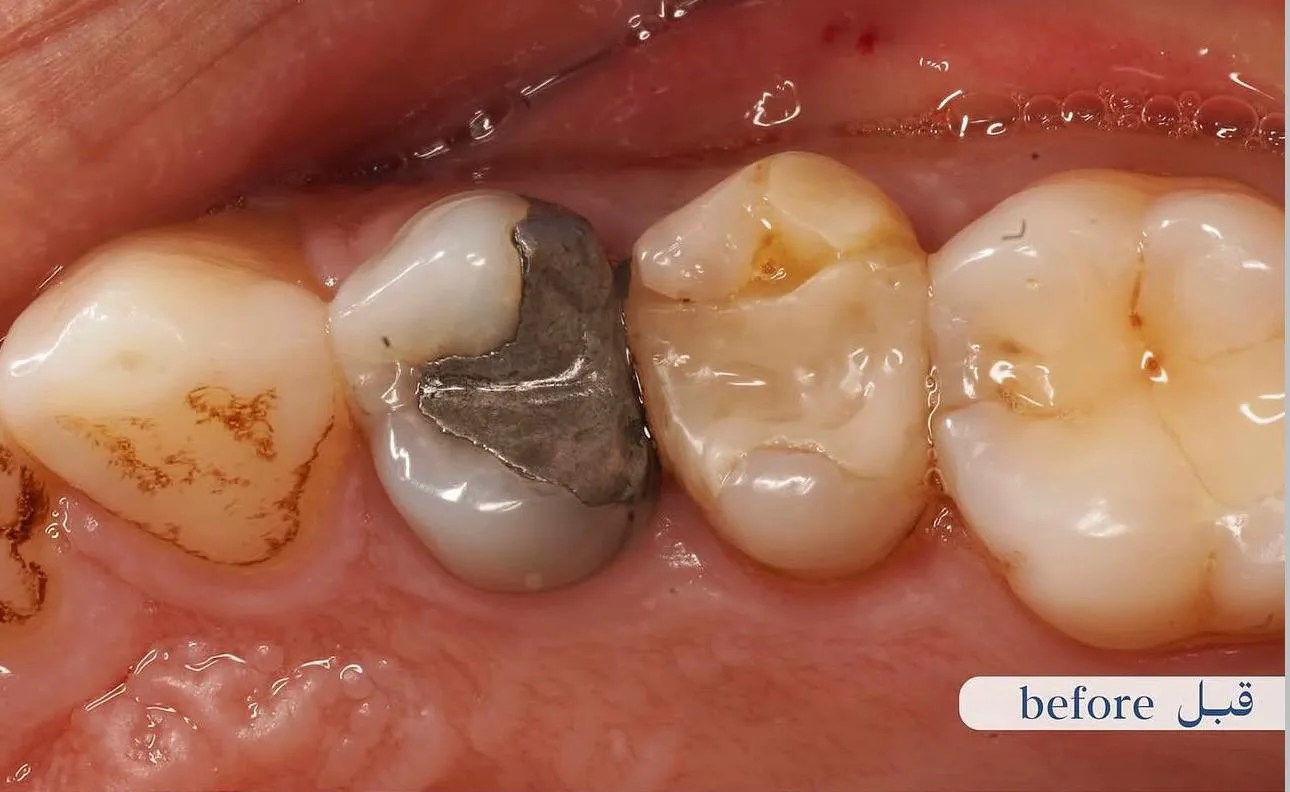

قبل